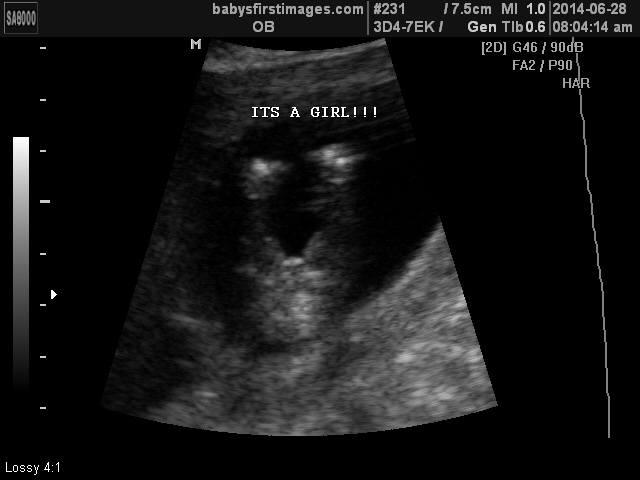

So I’m a couple of days late on the blog update… but it’s official – we’re having a girl! I’m going to steal the words from one of my aunts… I love when God’s plans fit with our desires. Amen! It is such a blessing that we’ll get to experience raising boys and a girl, and I truly feel as though our family will be complete come December. And I am especially excited for my husband because I know how much he wanted a daughter. I can’t wait to see him get to live that dream of having daddy’s little girl – it is going to be awesome!

We went into the ultrasound with a girls name picked out… we didn’t have a boys name, but it wasn’t for lack of trying, we really just couldn’t decide. But our girls name was set… we are naming her Berkley Elaine. Berkley was a name that my mother-in-law came across and we felt it fit well with Brogan and Beckett… unique, started with a B, two syllables, different end-sound, English/Irish origin, you know, all the things one thinks about when they are obsessively thinking about baby names on a daily basis. Elaine comes from Blake’s maternal grandmother who passed away. Â She was really special to many people, especially Blake, and I am sad that I never got to meet her. Our babysitter who recently passed away was also named Elaine, so for me, it’s an ode to her memory as well. Needless to say, I love her name. Love it. I can’t wait to see it embroidered on everything…. oh wait, it already is…